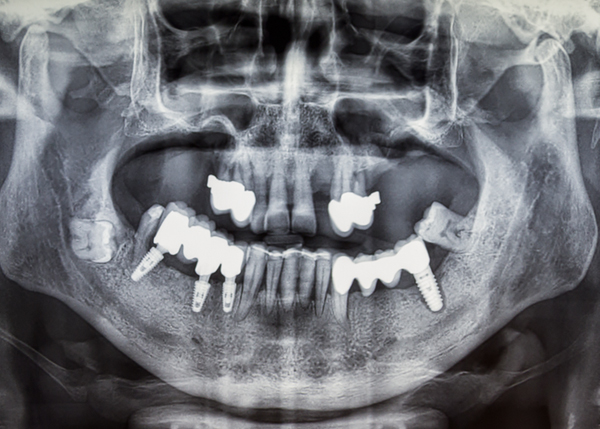

임플란트 식립 1만 례 이상

통합치의학과 전문의 대표원장의

고난도 임플란트 임상 노하우

수많은 임상경험과 해부학적 지식이 풍부한 대표원장이 다양한 디지털 장비를 사용해 환자 개개인의 구강 환경에 최적화된 맞춤형 치료 계획을 수립해 진행하기 때문에 다양한 고난도 케이스도 안전한 식립이 가능합니다.

성공적인 임플란트 식립을 위해서는 정밀한 진단이 필수적입니다. 3D 스캔·CT·CAD/CAM 기반의 디지털 분석으로 오차를 줄이고, 통합치의학과 전문의 대표원장이 직접 진단·설계·최종 보철까지 전 과정을 담당하여 심미적인 조화와 기능적 안정성을 동시에 고려한 임플란트를 제공합니다.

전악 임플란트

치아가 하나도 없거나 심각한 구강질환을 앓고 있어도

전악 보철을 제작, 임플란트를 치조골에 식립해

기능적, 심미적으로 자연치아와 가장 유사한 수준으로 재현이 가능합니다.